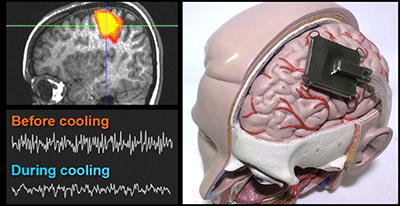

- Simulating effects of focal brain cooling against epilepsy